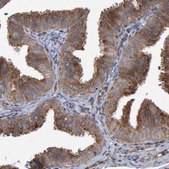

Application:

IHC

immunohistochemistry: 1:1000- 1:2500

由Atlas Antibodies提供技术支持的所有Prestige Antibodies®抗体均由人类蛋白质图集(HPA)项目开发和验证。每种抗体都通过针对数百种正常和疾病组织的免疫组织化学进行测试。通过单击图像库链接,可以在人类蛋白质图谱(HPA)站点上查看这些图像。我们还提供Prestige Antibodies® 抗体的实验方案和其他有用信息。

• 44例正常人类组织以及20例最常见癌症类型组织的IHC组织阵列。